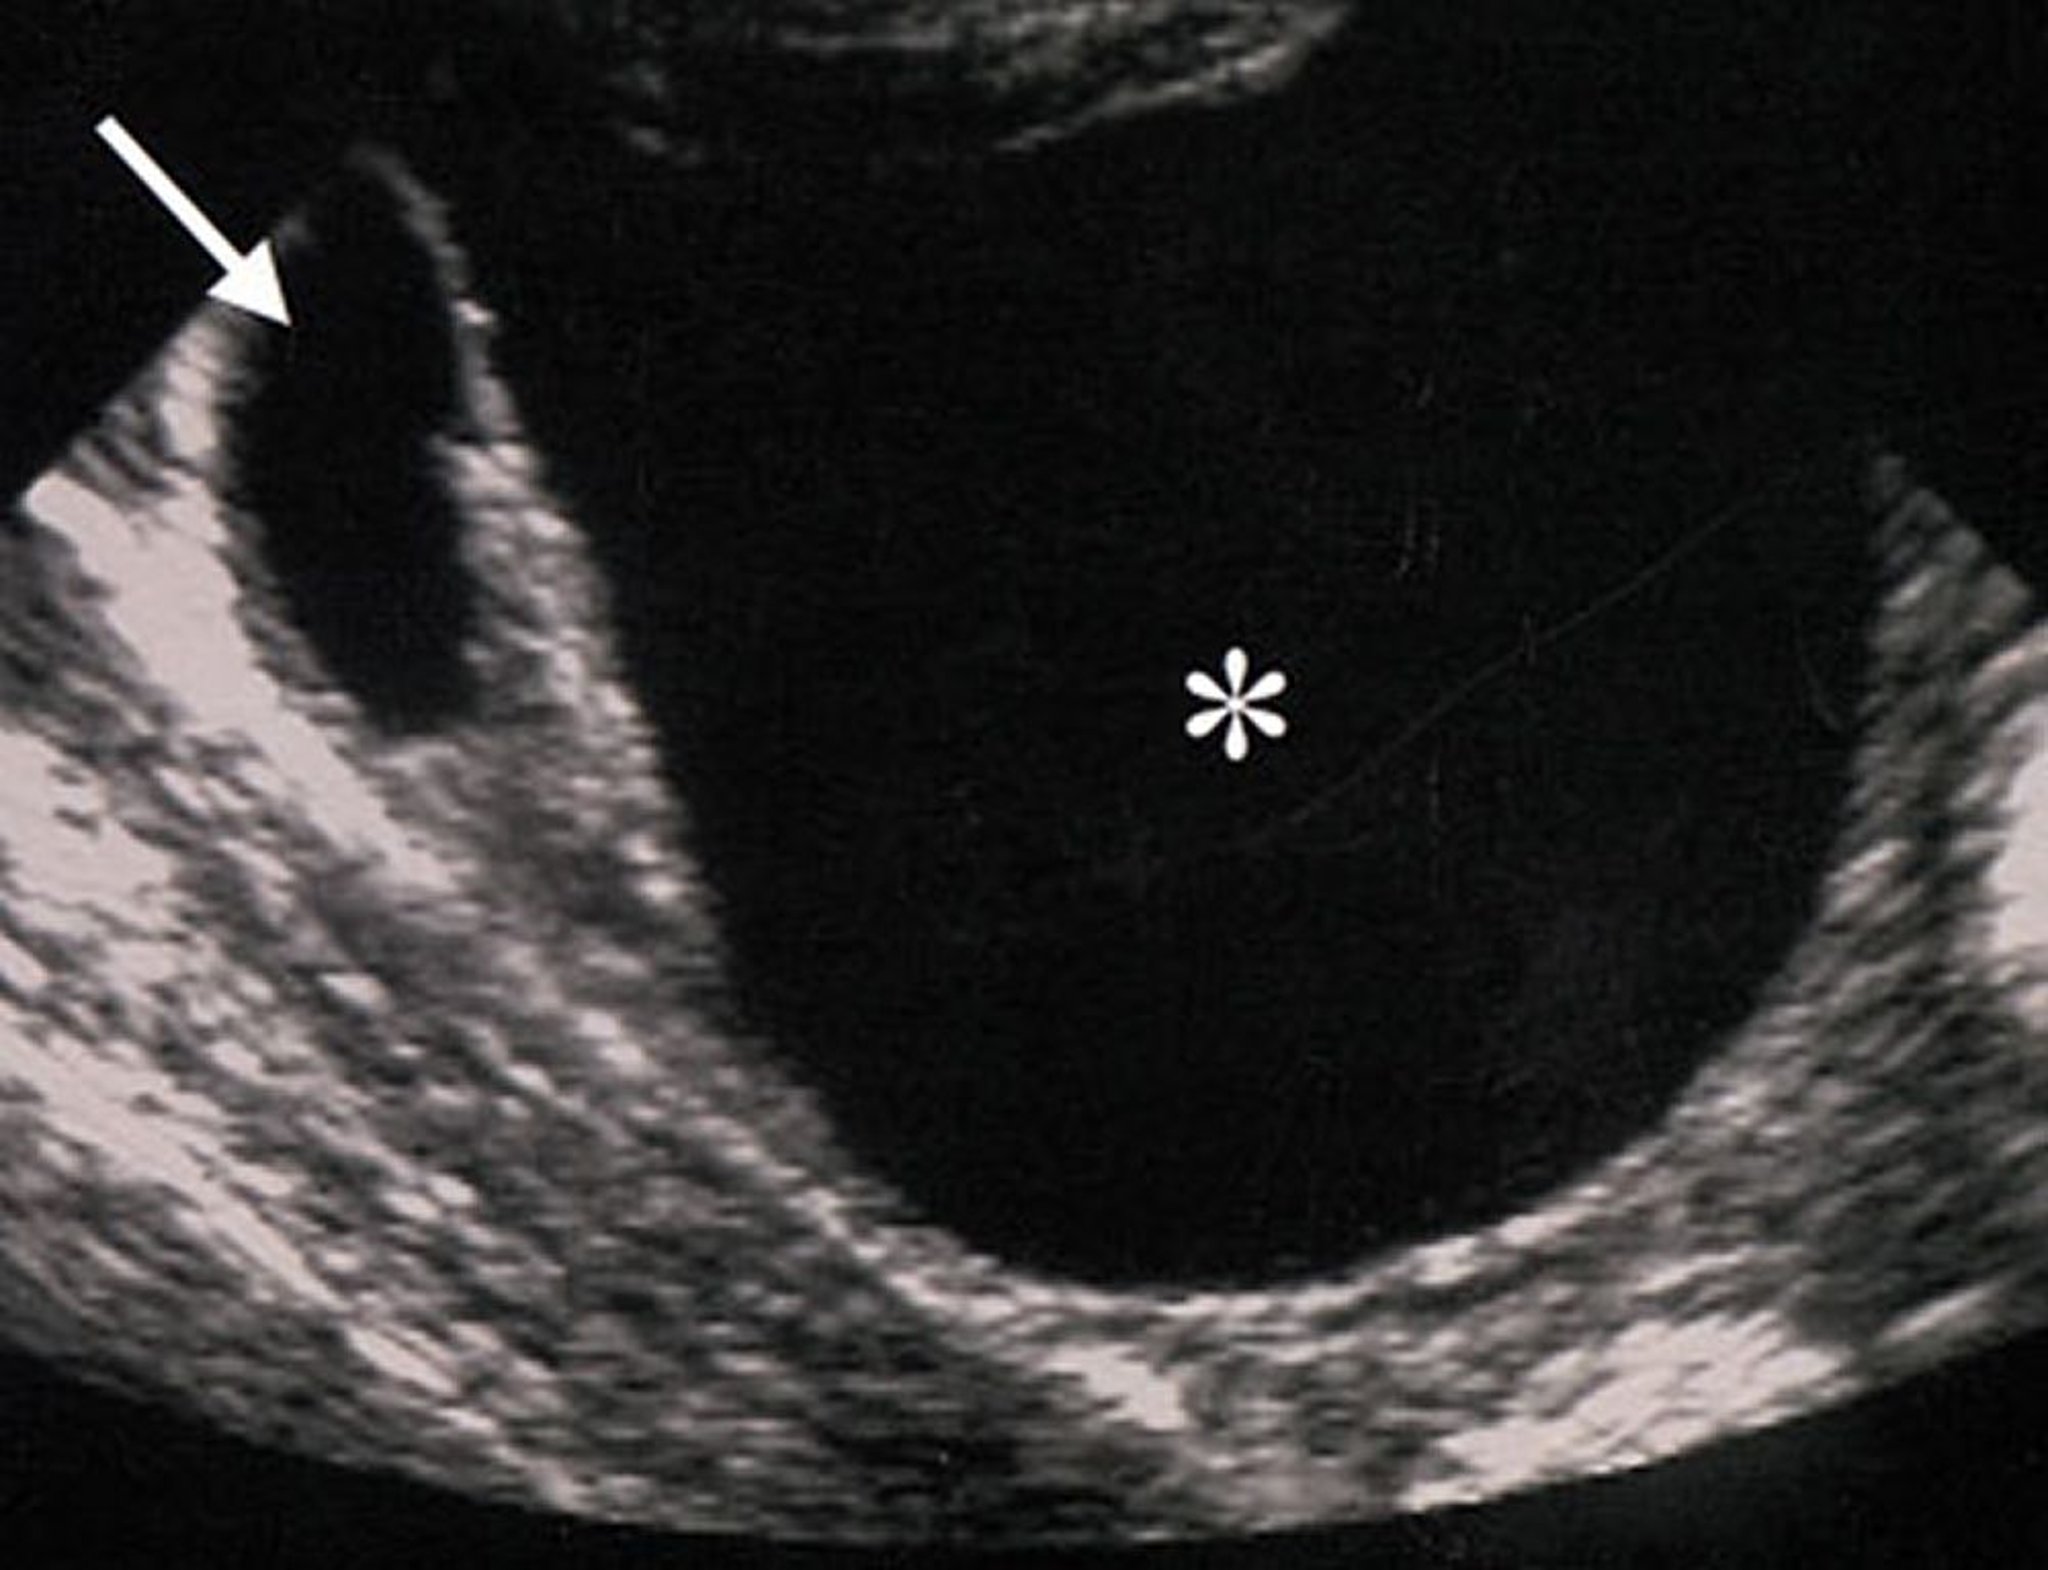

Ультразвуковые характеристики опухолевидных образований яичников (отмечены звездочкой), указывают на их доброкачественность. Образование анэхогенное (что говорит об отсутствии твердотелых элементов), правильной формы, с четкими краями, без утолщения стенок или патологических разрастаний.

By permission of the publisher. From Hricak H, Coakley F, Bergman A. In Atlas of Cancer. Edited by M Markman, RR Barakat, and WJ Hoskins. Philadelphia, Current Medicine, 2002.